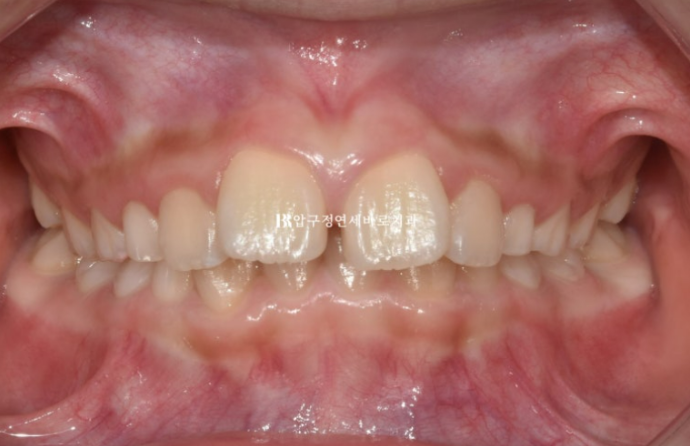

23.09

맞아진 위 아래 앞니 중심선과 개선된 과개교합

돌출된 앞니도 제자리로 들어갔습니다.